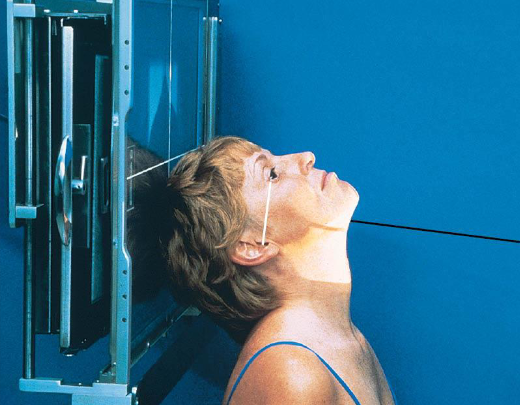

Tangential zygomatic arches

patient position:

upright (seated) or supine (torso elevated)

part position:

hyperextend neck and rest head on vertex

IOML as parallel with IR as possible

rotate MSP of head 15 degrees toward side being examined

tilt top of head 15 degrees away from side being examined

center zygomatic arch to IR

respiration suspended

CR:

perpendicular to IOML

centered to zygomatic arch 1 inch posterior to outer canthus

Tangential zygomatic arches image criteria